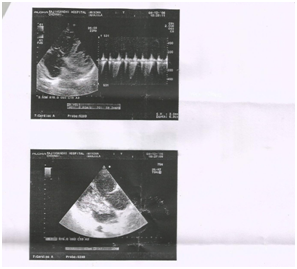

We present a 64_ year old female who presented with symptoms of dyspnea NYHA class III, and palpitations for two months duration. Clinical examination revealed pallor, and a mid diastolic murmur in mitral area. ECG was within normal limits. Echocardiogram showed a cauliflower like mass with multiple protruding villous appearance attached to the inter atrial septum near the foramen ovale traversing the mitral valve orifice causing mitral valve obstruction. Patient was referred to cardiothoracic surgeon for surgical excision (Figure 1 & 2).

Figure 1 Clinical examination 1.

Figure 2Clinical examination 2..